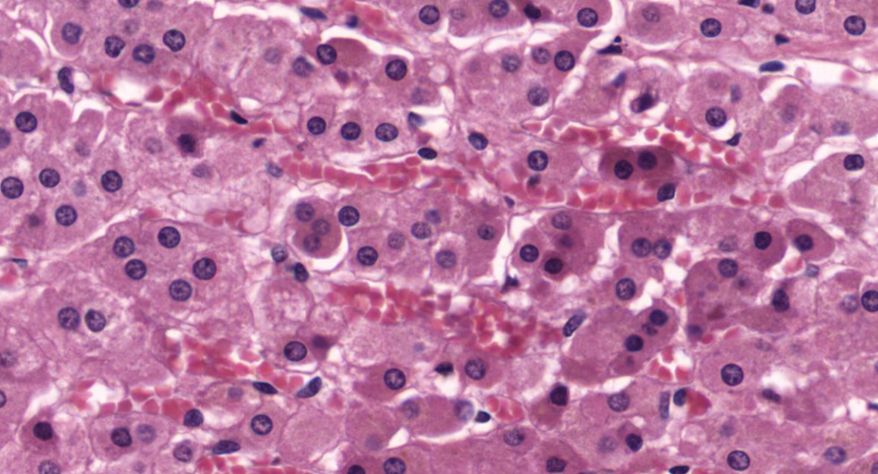

低倍镜观察:1. 被膜:由薄层结缔组织组成。2. 实质:由许多大小不等的滤泡构成。滤泡壁是单层立方上皮细胞,滤泡腔内充满粉红色匀质胶状物,滤泡之间的结缔组织内有丰富的血管。高倍镜观察:1. 滤泡:滤泡壁的单层滤泡上皮细胞一般呈低柱状或立方状,胞质着浅色,细胞核呈圆形。滤泡腔内充满了粉红色匀质胶质。2. 滤泡旁细胞:体积较大,呈圆形或椭圆形;细胞核较大,呈圆形,着色较浅,细胞质染色也较浅。细胞或嵌在滤泡壁上或成团分布于滤泡之间。3. 间质:由结缔组织组成。位于滤泡之间。其中含有丰富的毛细血管及三五成群的滤泡旁细胞。

1.全景图

2.滤泡

3.滤泡上皮细胞

4.胶质

5.滤泡旁细胞1

7.滤泡旁细胞2